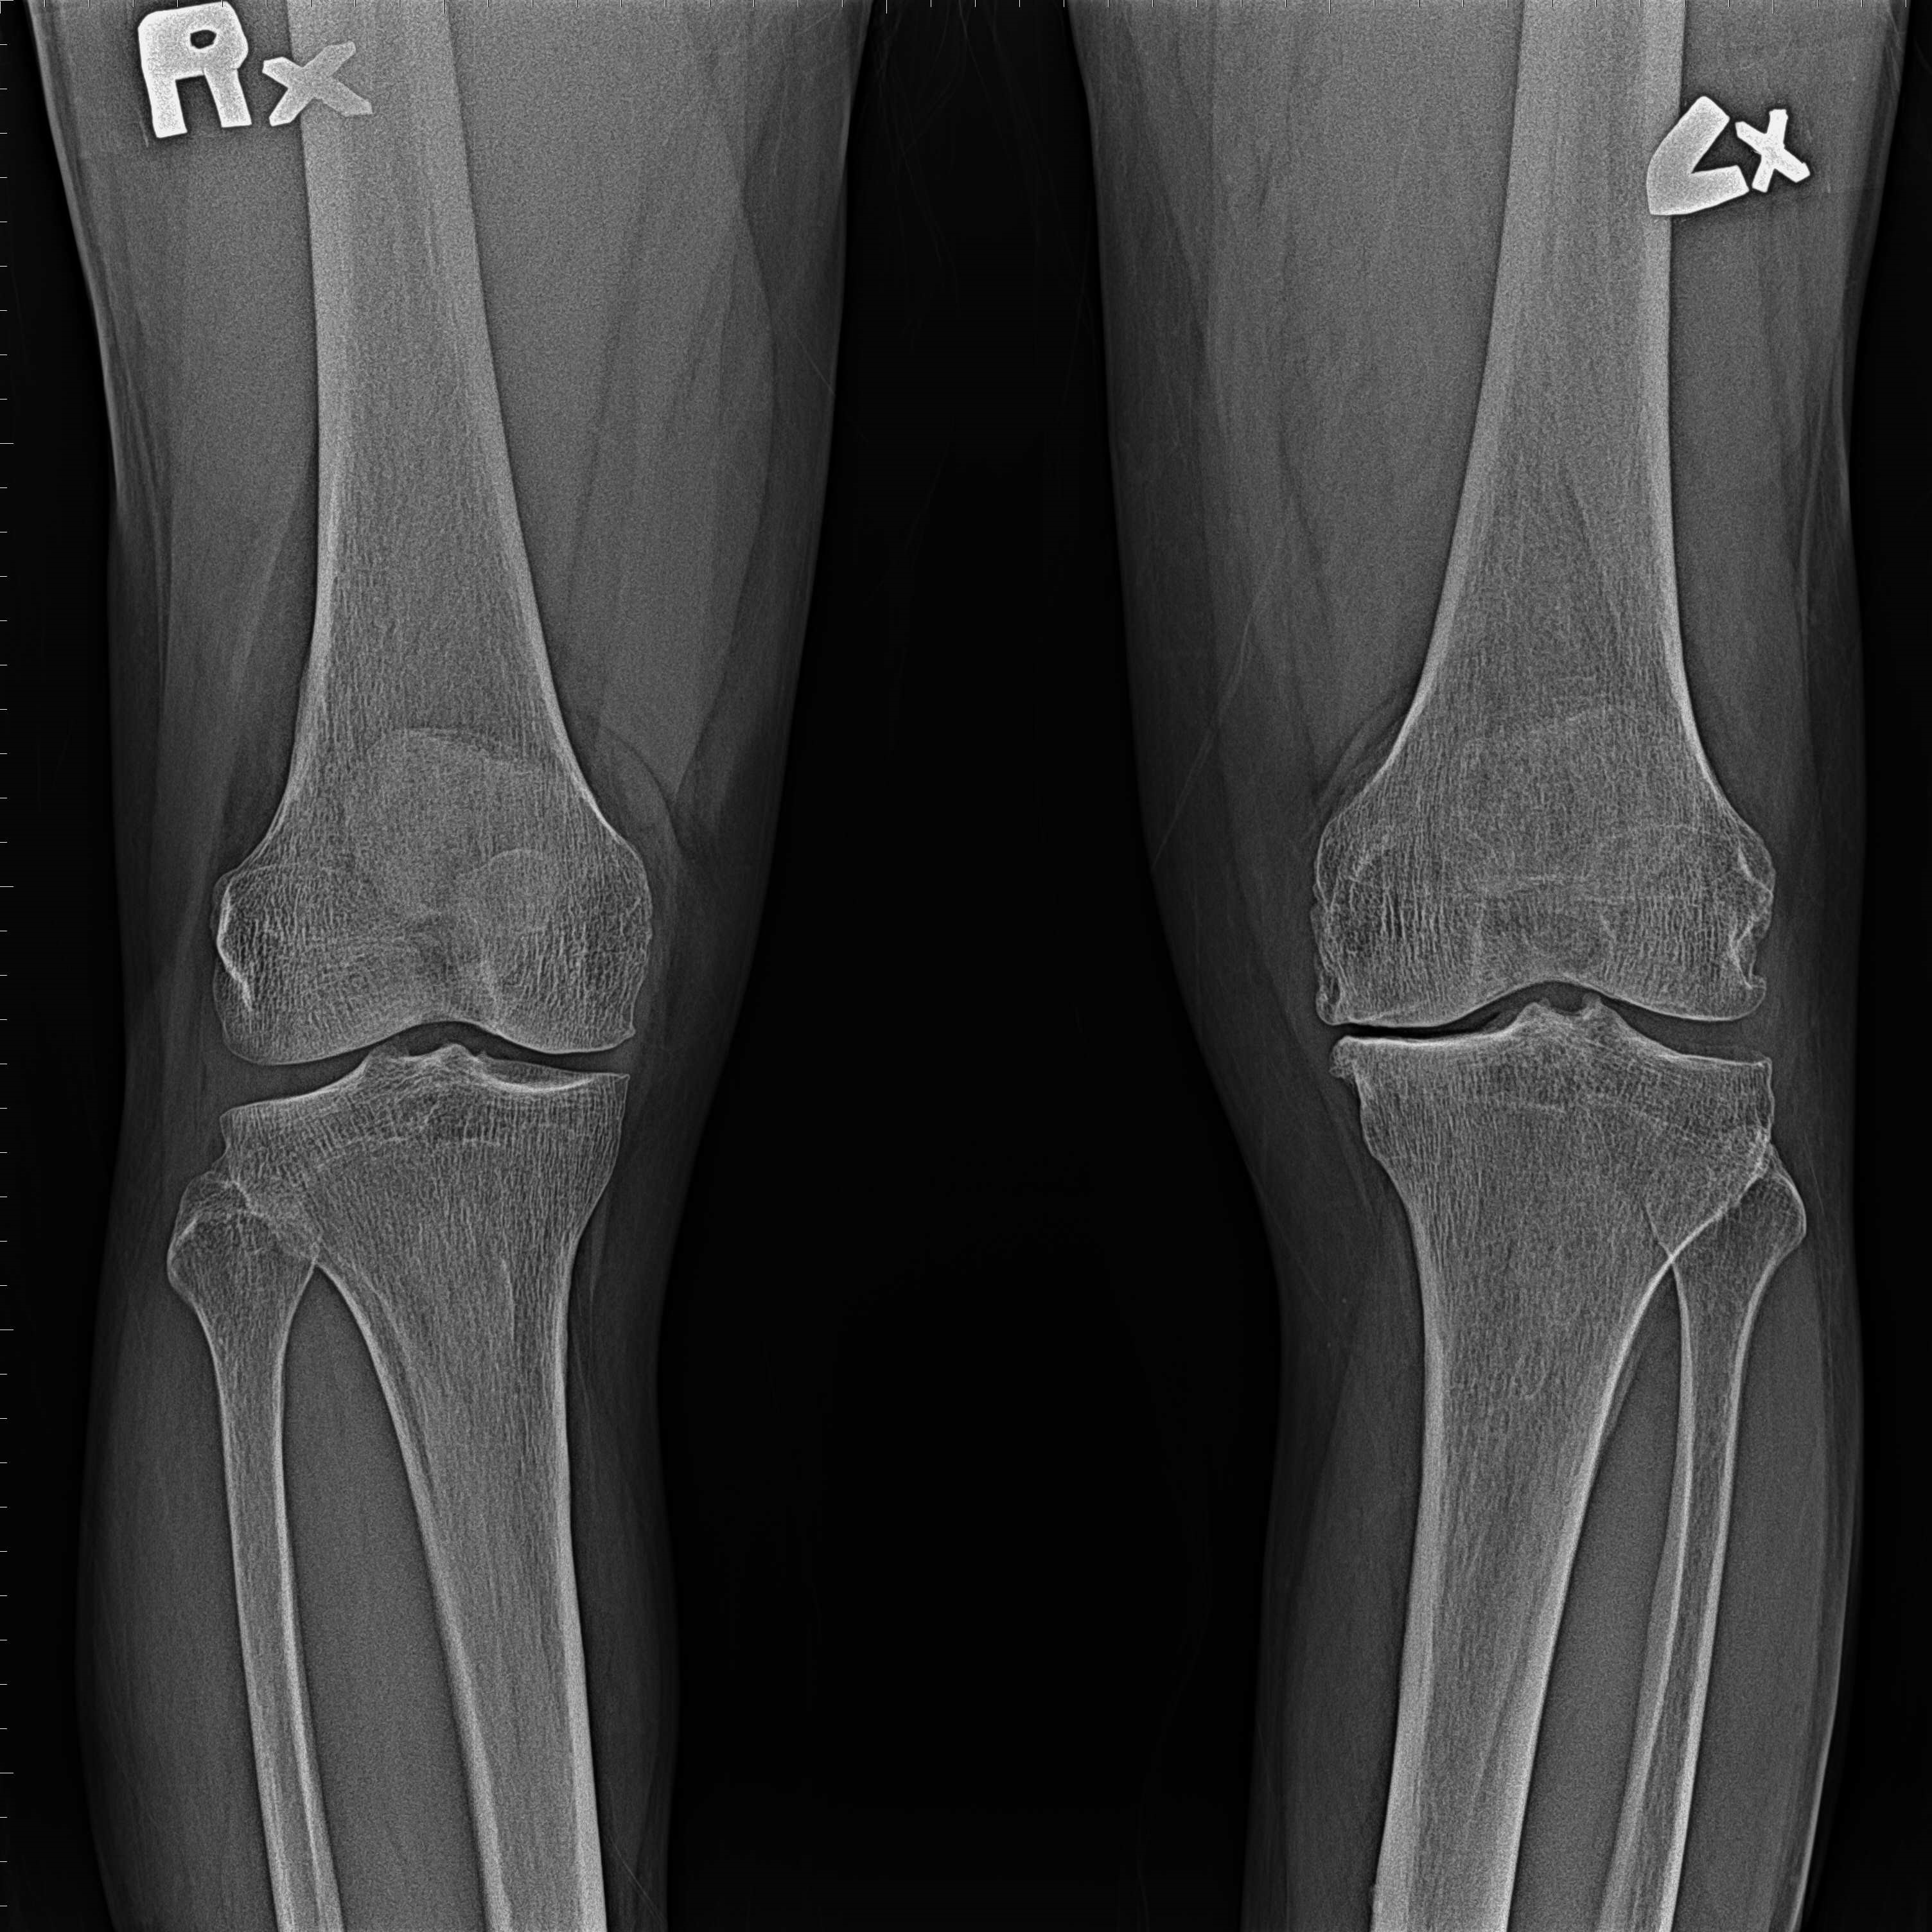

傳統部分膝置換 首頁 案例分享 膝關節手術 傳統部分膝置換 殷女士 65歲 術前 術後 張女士 71歲 術前 術後 蔡女士 74歲 術前 術後 張女士71歲 術前 術後 翁女士70歲 術前 術後 劉女士 80歲 術前 術後